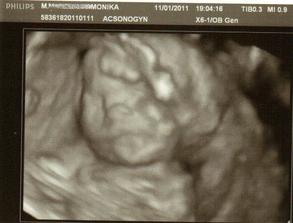

✿♥♥♥♥Bude to dievčatko!!!!! ♥♥♥♥✿

Bude to Stella 🙂

krasne 3D sono 🙂